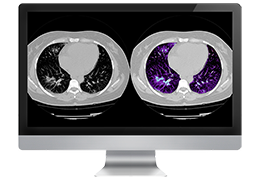

ART-Plan™ Artificial Intelligence Contouring